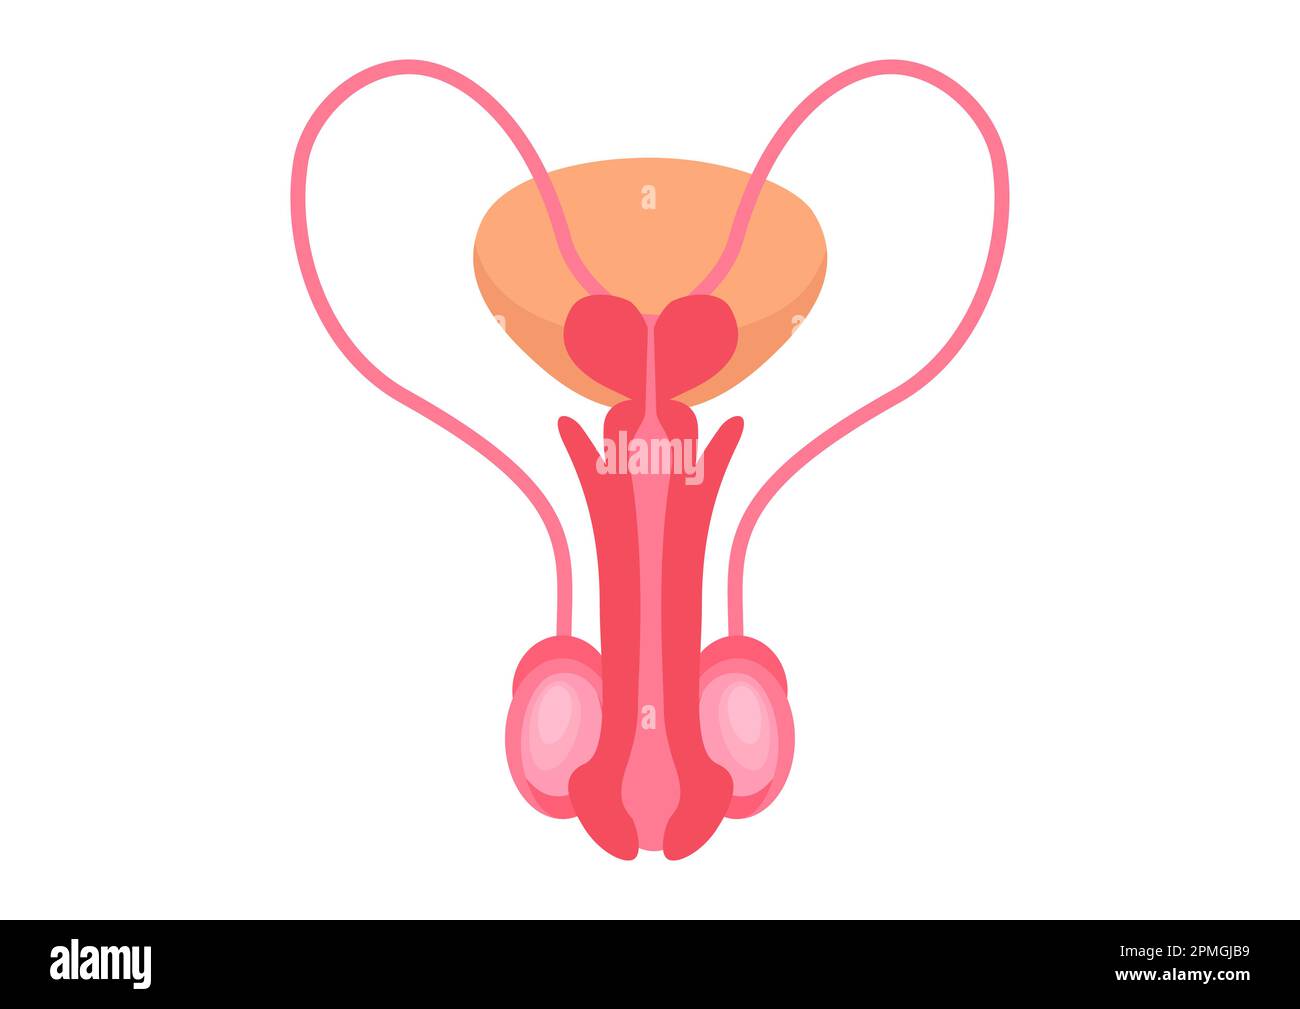

RF2PMGJB9–Männliche Fortpflanzungssysteme auf weißem Hintergrund. Vektordarstellung männlicher Fortpflanzungssysteme